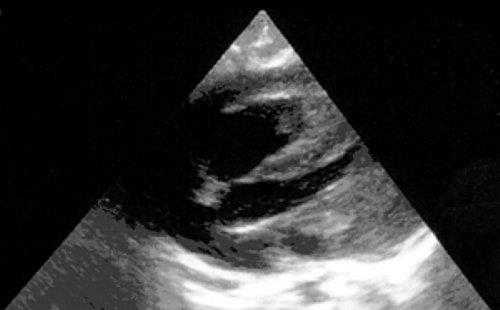

Широкое внедрение в практику ультразвуковой диагностики позволило перейти от аутопсийной статистики к прижизненному выявлению. Эхокардиография - первый метод выявления рабдомиомы сердца и контроля состояния пациента в динамике. Учитывая очень большое число семейных случаев, необходимо обследование всех ближайших родственников, особенно при наличии у них пятен цвета кофе с молоком, депигментированных по типу шагреневой кожи, параунгвальных и параореолярных фибром, ранних миом матки, инфантильных спазмов, судорожных припадков и других признаков факоматозов. При семейных обследованиях рабдомиомы сердца могут выявляться у совершенно бессимптомных носителей (рис. 1, 2).

Рис. 1. Эхокардиограмма ребенка (девочки) с рабдомиомой. Крупный узел рабдомиомы в межжелудочковой перегородке (1) и менее крупные узлы в задней стенке левого желудочка (2). Эхоплотность образований выше, чем миокарда.